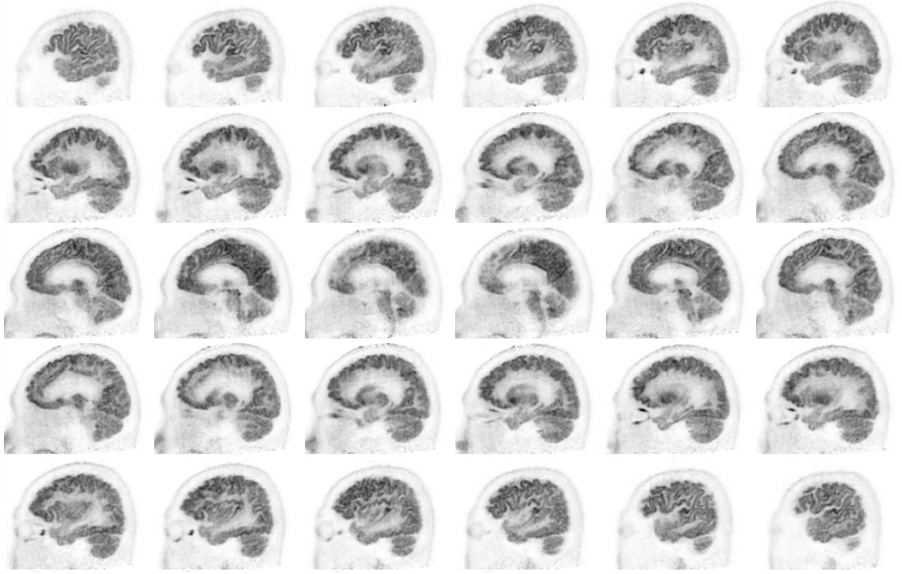

Head / Case2 : FDG

Sagittal

Courtesy : Kindai University Hospital

- Imaging protocol

- Injected dose: 3.29 MBq/kg, 18F-FDG

- Uptake time: 38 minutes

- Scan time: 30 minutes